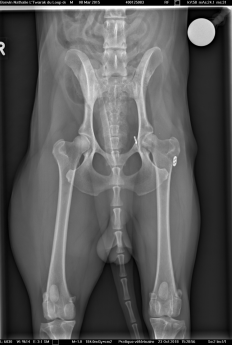

Voici les radios du 23 octobre... la tête du fémur est nécrosée...sur problème infectieux... je ne suis pas contente... la seule alternative qu'il reste maintenant et de tout enlever, de couper la tête du fémur... et Twarak devra vivre ainsi.

Il me dise que pour un chien comme lui, c'est très gérable... je suis triste pour Twarak....